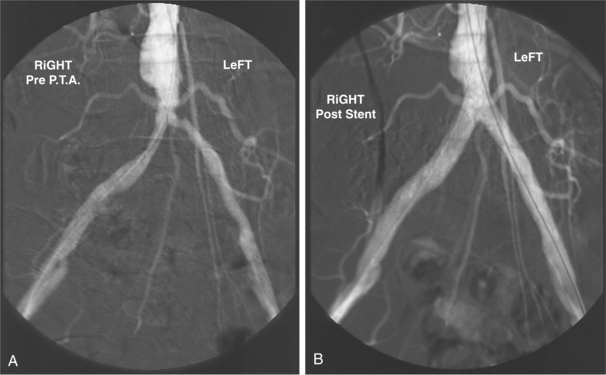

Surgical intervention (revascularization procedures such as bypass graft or angioplastic treatment; Fig. 12-31) is indicated if blood flow is compromised enough to produce symptoms of ischemic pain at rest, if tissue death has occurred, or if claudication interferes with essential activities or work.68 This decision is usually made after exercise therapy combined with risk factor modification has been unsuccessful in preventing this level of impairment and subsequent disability.

Figure 12-31 Percutaneous transluminal angioplasty (PTA) may be used in peripheral vascular disease. A, Significant narrowing of the aortic bifurcation and both common iliac arteries. The narrowing in both iliac arteries was successfully treated by angioplasty, and bilateral stents were inserted to maintain patency. B, The client had presented with bilateral calf claudication, which was relieved by this procedure. (From Forbes CD, Jackson WF: Color atlas and text of clinical medicine, ed 3, London, 2003, Mosby.)

Cessation of smoking may be required by the physician before surgery is considered. Persons with localized occlusions of the aorta and iliac arteries less than 10 cm in length, with relatively normal vessels proximally and distally, are good candidates for angioplasty or stenting (see Figs. 12-3 and 12-5). Conversely, people with multisegmented arterial disease with more involved symptoms are at greater risk of amputation. Endovascular intervention includes a variety of catheter-based surgical techniques that are being improved by laser techniques.